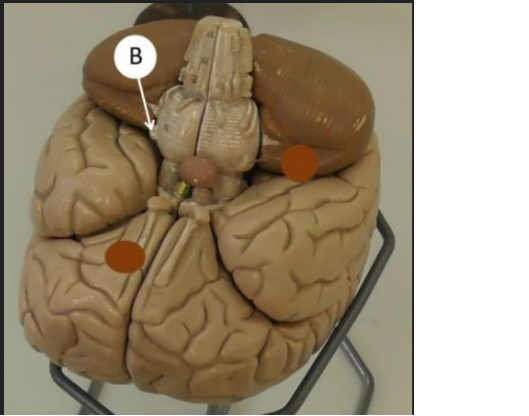

nucleus caudatus dex.

lobus parietalis Dex.

lobus temporalis sin.

medulla oblongata

mesencephalon

hippocampus dex.

tonsilla cerebelli sin.

pyramis sin. medullae oblongatae

pons

crus cerebri Dex.

radix n. trigemini sin.

Vermis cerebelli

hemisphaerium dex. cerebelli